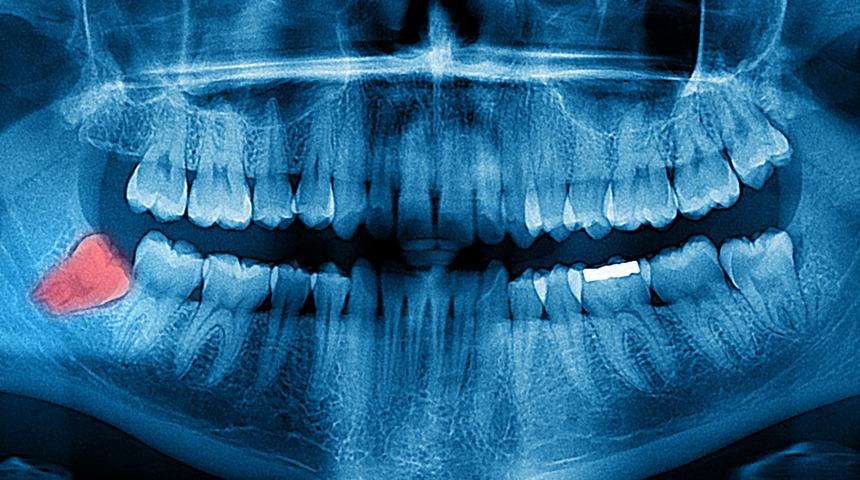

Yeni bir araştırmaya göre insanların yiyeceklerini çok fazla işliyor olması, 20 yaş dişlerine ihtiyacı ortadan kaldırıyor. Bu nedenle de gelecek nesillerde 20 yaş dişleri tamamen yok olabilir.

Söz konusu çalışmaya öncülük eden Dr. Teghan Lucas, insanların yiyecekleri ateşte pişirmeyi ve daha fazla işlemden geçirmeyi öğrendikçe, 20 yaş dişlerine olan ihtiyacı kaybettiğini ifade etti. Dr. Lucas’a göre bu değişim, yalnızca yeni nesillerin 20 yaş dişleri olmadan doğmasına neden olmuyor, aynı zamanda çenenin daha az dişe paralel olarak daha küçük yapılı hale gelmeye başlıyor.